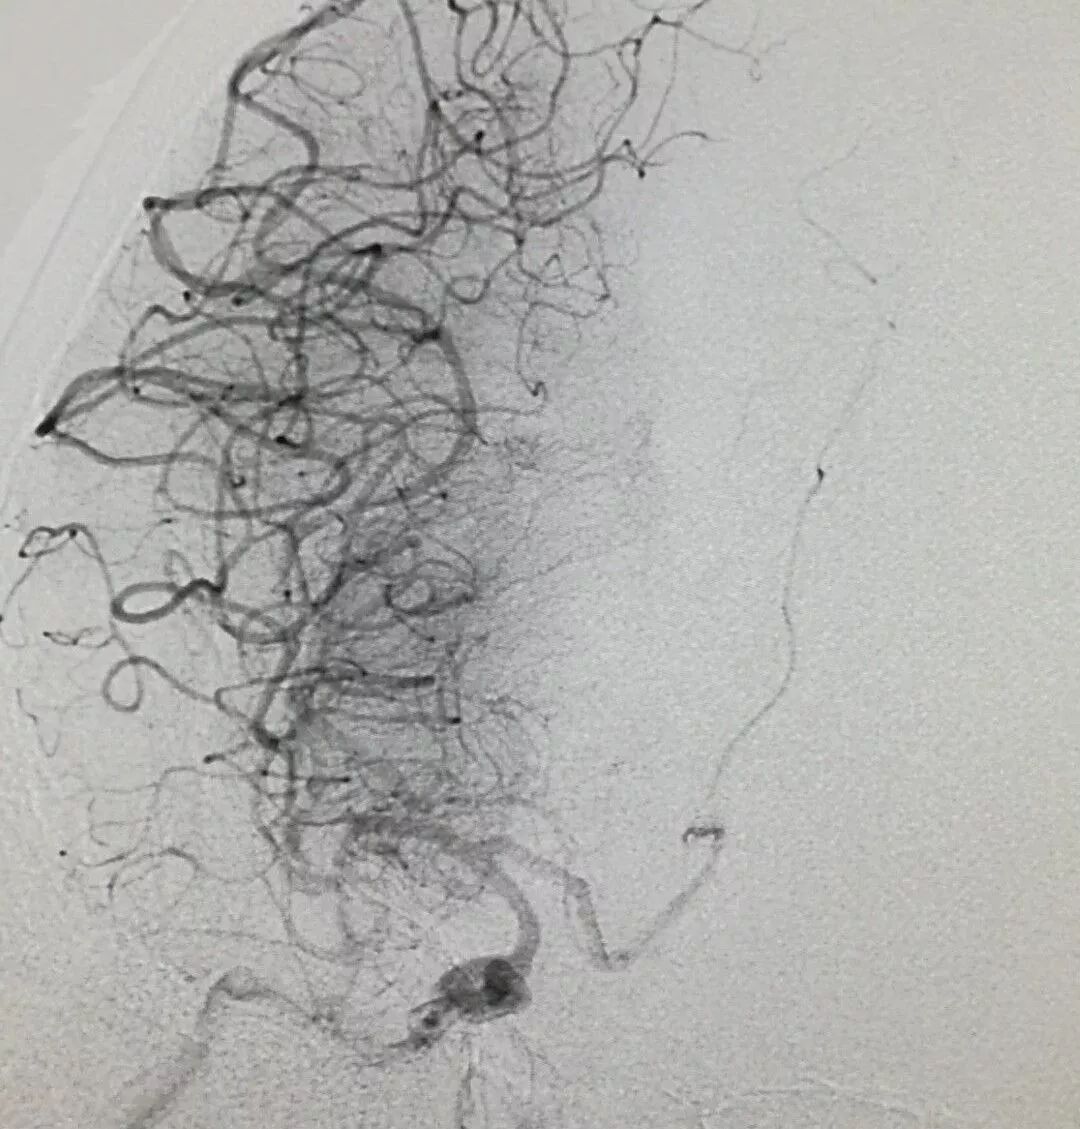

靜脈溶栓治療后,患者血管未能開通,經(jīng)與家屬溝通,張騏主任決定對(duì)患者行緊急全腦血管造影+機(jī)械取栓。神經(jīng)內(nèi)科卒中小組當(dāng)即會(huì)同神經(jīng)外科、介入科、麻醉科、影像科、導(dǎo)管室等相關(guān)科室組成的搶救團(tuán)隊(duì)共同為患者行機(jī)械取栓治療。造影顯示患者右側(cè)頸內(nèi)動(dòng)脈起始段和右側(cè)頸外動(dòng)脈起始段均閉塞,搶救團(tuán)隊(duì)密切配合,熟練的將取栓支架置入血管取出栓塞斑塊,兩次取栓先后順利完成,造影顯示動(dòng)脈已順利開通。